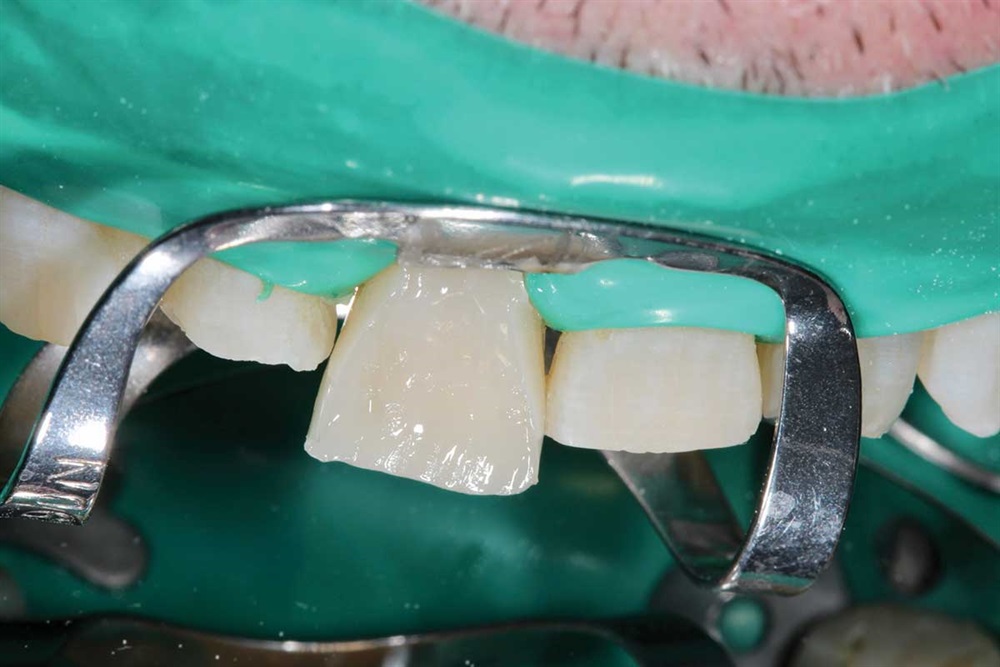

Fig. 27: Starting the maxillary teeth with 90N, rubber dam and Premier Cure-Thru contoured matrix band. Incisal view.

Fig. 28: My first increment is Z250 to provide palatal support, and then I cover that with Renamel A1.5.

Fig. 29: I cut an increment off the end of my Renamel syringe, flatten it between my finger and thumb and place on the labial of the tooth. I apply a little bonding resin on the composite increment to reduce pull-back, then work it into the interproximal and cover the tooth. Takes some time, because it does not flow like Z250.